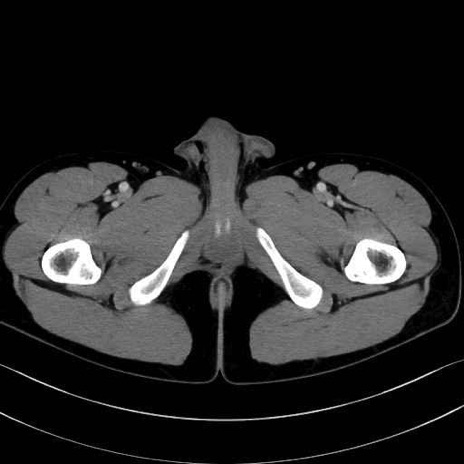

大腿方形筋 (Quadratus femoris)